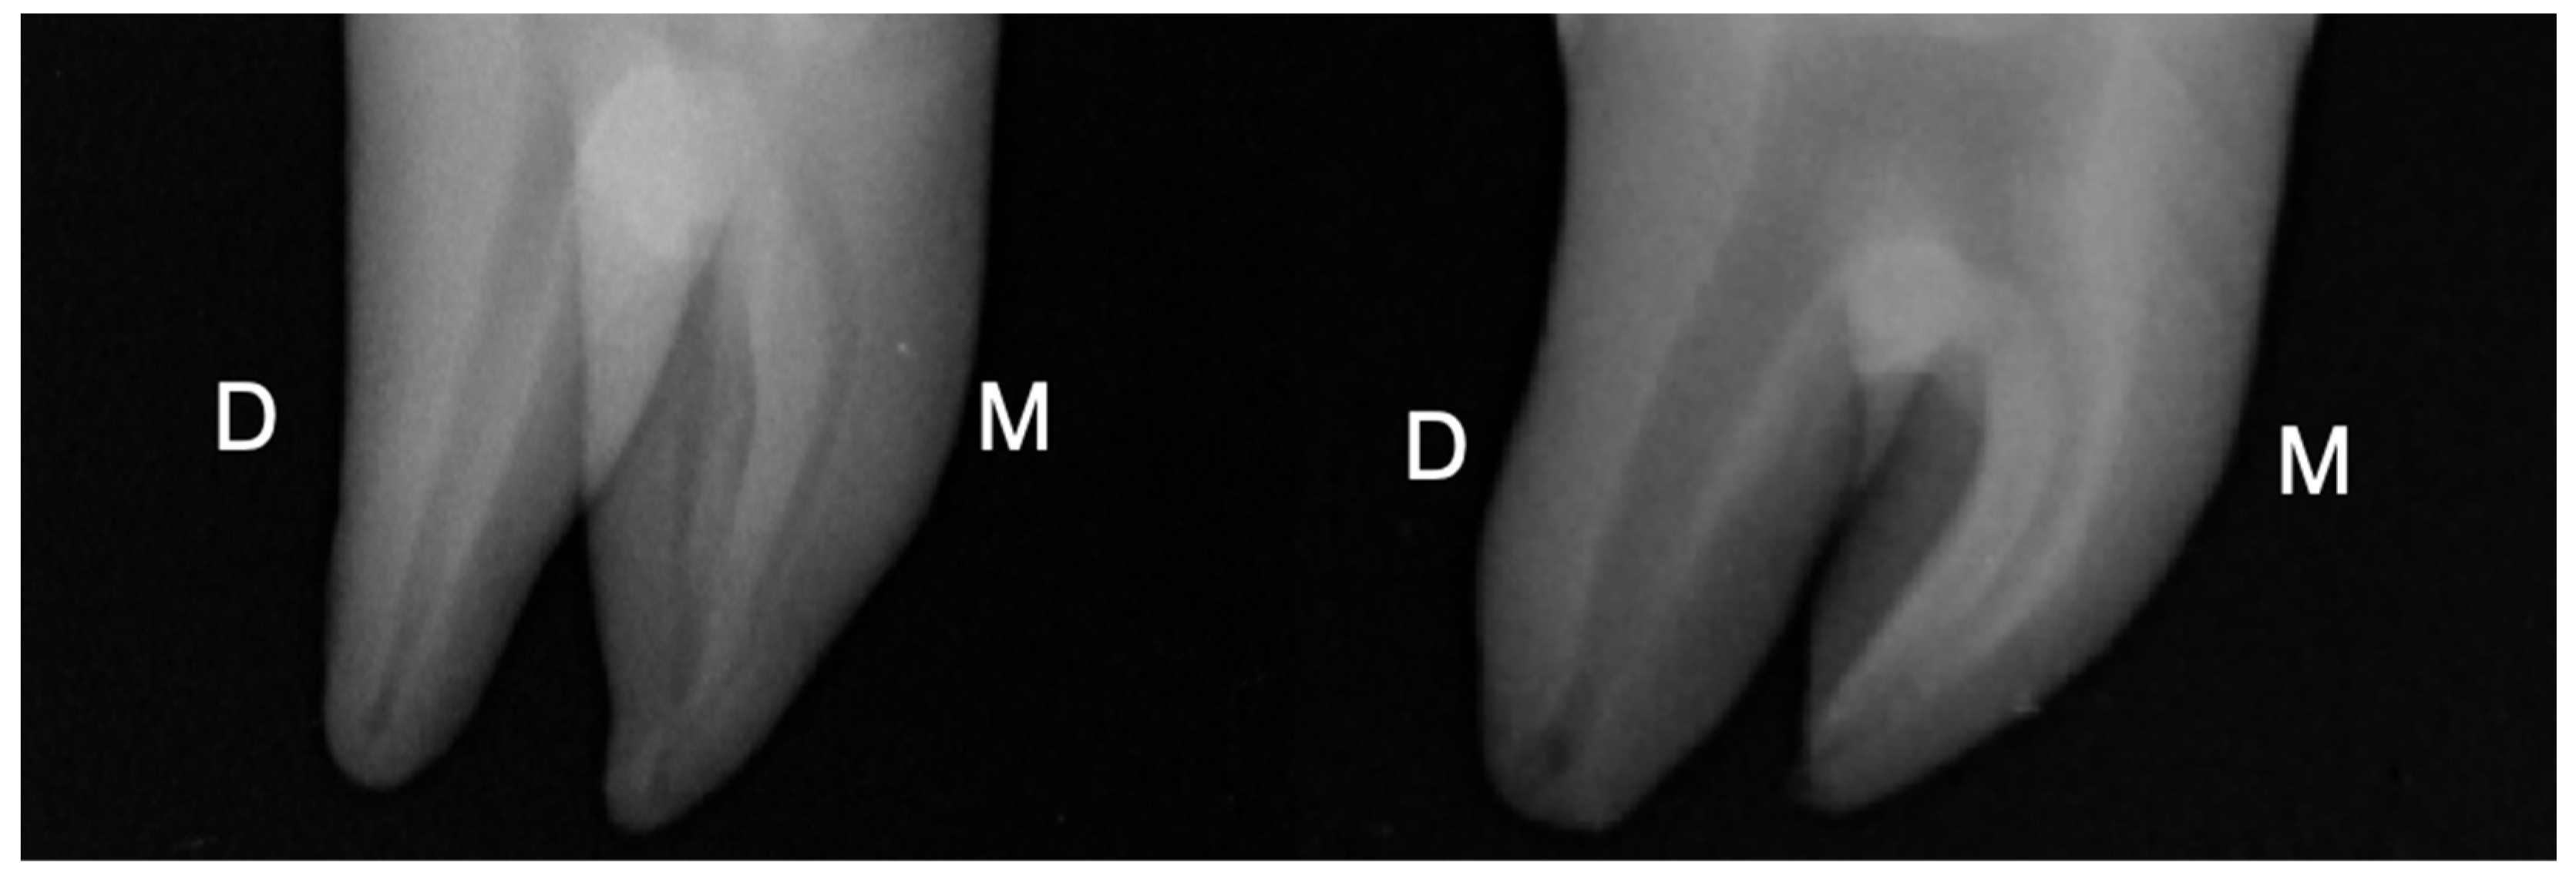

The Ethics committee of Saint Joseph University, Beirut, Lebanon provided the ethical approval (FMD184). Following a previous pilot study, sample size was determined for ensuring a power of 80% and α = 0.05 using G*Power 3.1.9.2 software (Heinrich-Heine University at Dusseldorf, Dusseldorf, Germany). Based on these parameters, a number of 10 samples for group was determined. Hence, a total of 20 intact human mandibular molars recently extracted for periodontal reasons were included. The selection criteria consisted of teeth with intact crowns exempted from fracture lines or cracks, caries, any previous restoration, and molars with one distal root with completely formed apices and an oval shape 5 mm below the root apex. This parameter was confirmed by periapical radiography in the mesial-distal (MD) and buccal-lingual (BL) directions. The canals were considered as oval when the BL diameter was 2.5 times larger than the MD diameter [12] (Figure 1).

Figure 1.

Periapical radiographs of two mandibular molars selected for the study. D: distal, M: mesial.